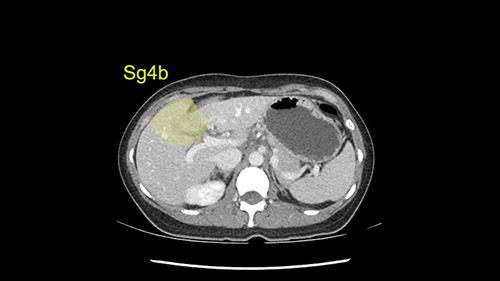

We note that the tumor is pushing on the gallbladder but I think that’s probably external for the most part. I think that’s extrahepatic. I believe that Segment 4b is probably free of tumor. I’d have to say that it's tempting, particularly looking at the coronals, to consider a very limited resection. Where you’d just chip it off the bottom of Segment 3 and do a limited Segment 3 resection. I’d be concerned about the oncologic margins. I believe that the best oncologic operation will be to take the left portal vein to get this. Certainly, she’s got plenty of liver and she’d be able to sacrifice Segments 2-3 of the left lobe of the liver. It’s not necessary to take too much of thus of Segment 4a. But once one takes the portal vein, that will be compromised. So I would do a left hemihepatectomy on this woman.

Tumor proximity to Sg4b

The tumor is so close to the falciform ligament, I had a question mark about the Segment 4b relation between segment 4b and segment 3. In a normal resection of segment 2 and 3, we would be keeping on the left side of the falciform ligament and start getting segment 3 and 2 portal pedicles but in here its getting so close. So oncologically, 4b should be checked during the OR.

When you see the axial sections of the scan, you find it's a largely exophytic mass and its well-encapsulated. So this is typically true of a well-differentiated hepatocellular carcinoma. If you look at this, this is the gallbladder which is being displaced to the right and the mass is in the Sg4 of the liver, exophytic, projecting down. As it is coming down, it is also displacing the duodenum and the head of the pancreas which is being pushed towards the left and it's going right up to the cava, the start of the anterior surface of the cava. Obviously getting a lot of collaterals and vascularity from all the vessels around but one has to be very careful in evaluation of the main portal pedicle in this particular case and of course arterial inflow to the Sg4 and of course the left lobe of the liver.

What kind of procedure can we plan for this patient? It obviously has to be a left hemihepatectomy because most of the lesion is actually in Sg4. Can we do something which is less than a hemihepatectomy and just do only a segmental resection? The answer to that is that this vascular supply, if you are trying to ligate only the portal venous pedicle to the Segment 4, it is very close to the tumor and you will end up not having not a great margin as far as tumor resection is concerned so I would recommend a left hemihepatectomy and not just a partial or segmental resection. You can also see that it is crossing the falciform line and going on to Segment 2 and 3 so trying to do anything less than a left hemihepatectomy may not give the right kind of margins which we need for this tumor. Fortunately for us, the contours of the liver, which are very important to see in a Hepatitis B patient, there are no cirrhosis which I can see. The normal liver functions indicate that it's a well compensated Hepatitis B.